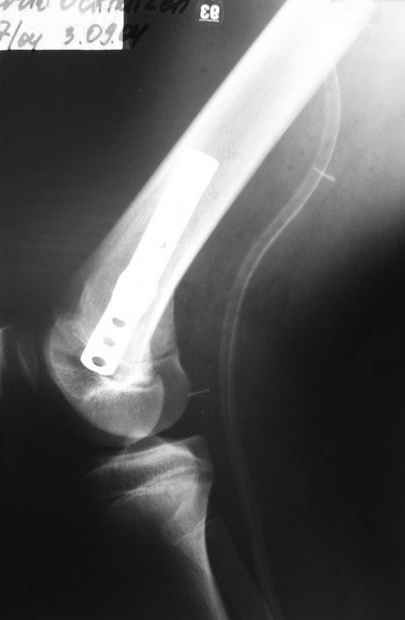

Как вариант решения прогрессирующей вальгусной деформации коленного сустава я бы предложил косую остеотомию дистального отдела бедра с фиксацией пластиной и компрессирующим винтом.

Взгляните на снимки , может быть это вам поможет.

Около 5 лет применяю этот тип дистальной остеотомии бедра для коррекции механической оси Н/К ( более 20 случаев) - достаточно эффективная операция.

Было одно осложнение у молодого пациента - ятрогенное повреждение бедренной артрерии, которое решилось васкулярной пластикой без каких -либо последствий для функции конечности.